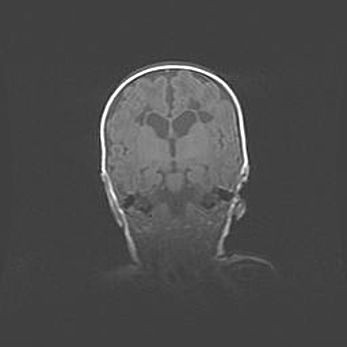

Наружная гидроцефалия с возможной атрофией височных областей.

Возраст: 28 дней

Вес: 3670 г

Пол: мужской

Окружность головы: 38 см

Срок гестации: 40 недель

Гидроцефалия головного мозга у новорожденных – это заболевание, которое характеризуется скоплением избыточного количества спинномозговой жидкости в желудочковой системе головного мозга в результате затруднения её перемещения от места выработки к месту поглощения в кровеносную систему или вследствие нарушения абсорбции. При открытой наружной форме гидроцефалии у новорожденных расширяются и переполняются субарахноидные пространства.

При нормотензивных  формах,  которые,  как  правило,  являются  следствием  перенесенных ишемических  повреждений  паренхимы  мозга,  возможно  сочетание микроцефалии  с нормотензивной гидроцефалией. В основе данных изменений лежит атрофия больших полушарий с преимущественной  локализацией  в  лобно-височных  областях.